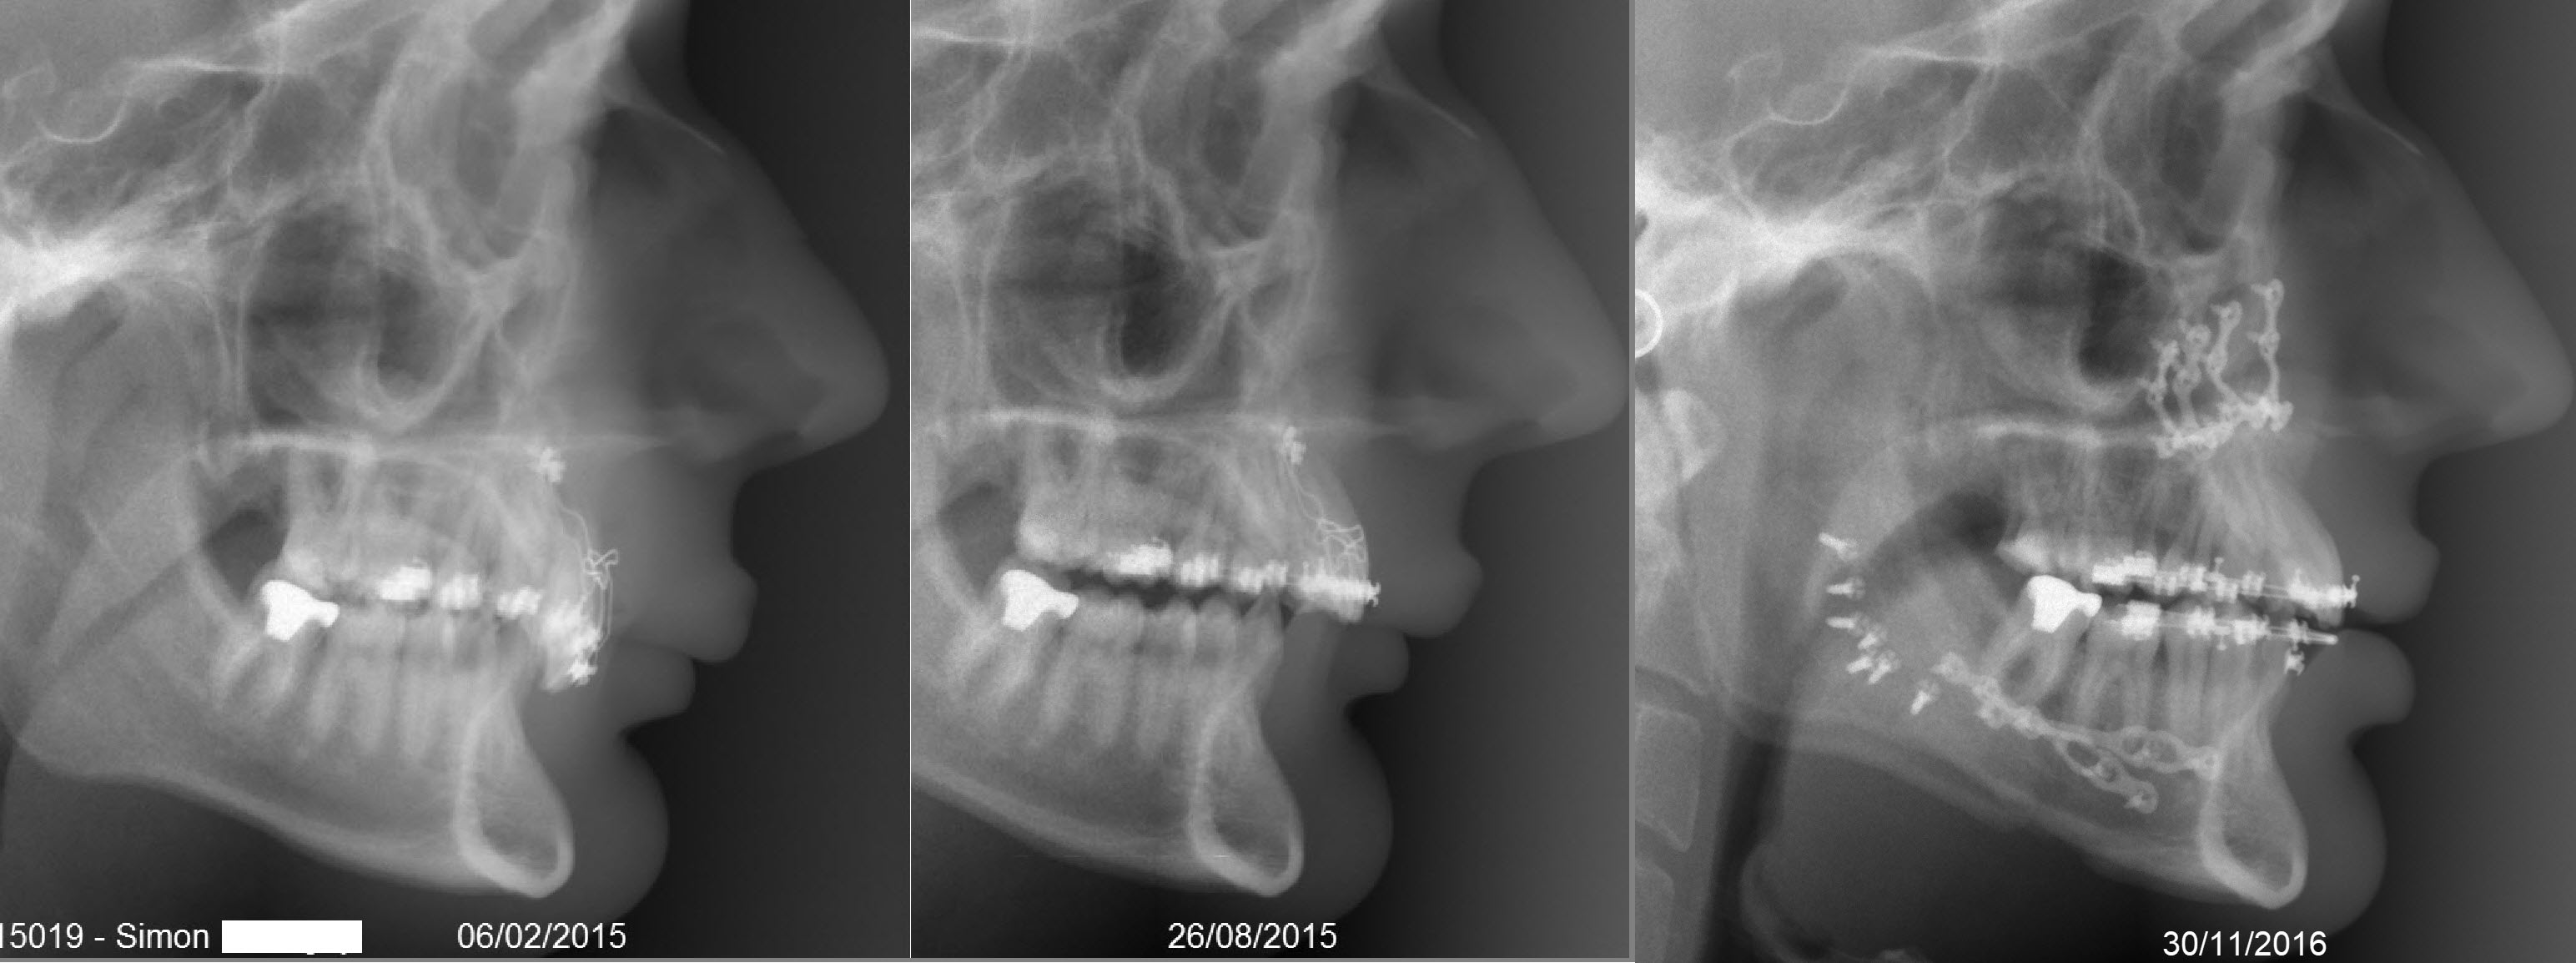

Je pensais d’ailleurs que des attaches « libres » étaient une condition nécessaire, cet autre cas (clichés joints) prouve que non : c’est un cas chirurgical avec des braquets traditionnels bi-ailettes. Cas d’agénésies multiples (dont absence d’incisives inférieures). L'ingression des incisives supérieures a été réalisée avec un arc en fil rond et des ancrages osseux sur microvis enfouies para-piriformes (posés ici, au cabinet). Tu peux observer le recul spontané des apex des incisives, sans avoir donné d'information dans ce sens aux braquets. A méditer.

15019 simon torque epzx6d - Eugenol